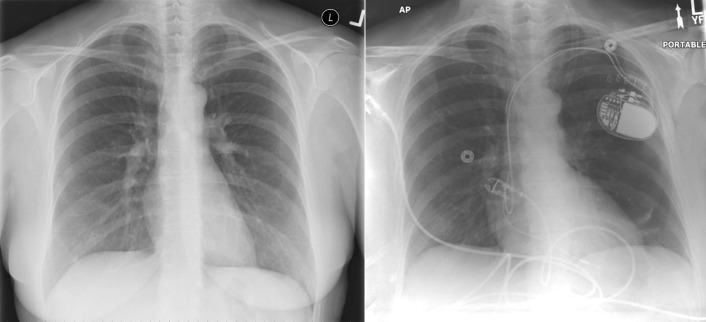

Chest radiography has a standard role in the identification of several potential complications such as pneumothorax, hemothorax, and several forms of malposition after insertion of pacemakers, implantable cardioverter defibrillators (ICDs), and cardiac resynchronization therapy devices.

Pacemaker leads are apparent, and ICDs are more obvious because of their larger coils. Coronary sinus leads for cardiac resynchronization therapy are finer leads.

Endocardial Pacer Leads

The position and integrity of endocardial pacer leads should be verified, especially when pacemaker dysfunction is clinically suspected ( Graphics 23-1 to 23-4 ; Figs. 23-1 to 23-15 ).The most common cause of pacemaker dysfunction that is apparent on the chest radiography is distal lead displacement/misplacement.

With a right atrial lead , the tip should be in the right atrial appendage.

With a right ventricular lead , the tip should lie anteriorly at the apex of the heart.